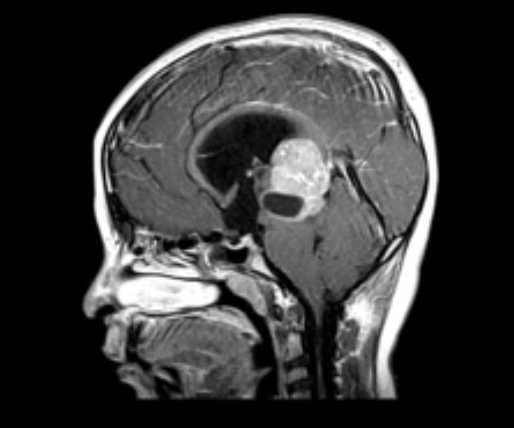

Como caracteriza-se o nistagmo em retração-convergência?

Nistagmo associado à paralisia do olhar conjugado vertical para cima. Na tentativa de olhar para cima, o olho faz convergência

Pensar em Síndrome de Parinaud ou síndrome do mesencéfalo dorsal (principal causa = pinealoma)